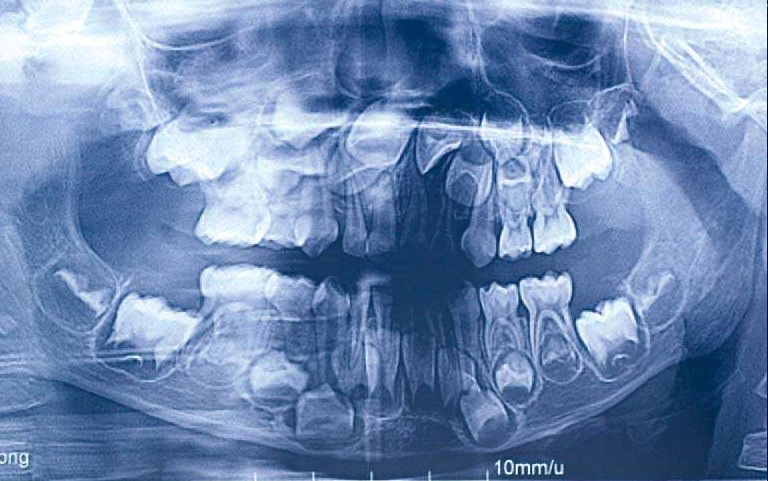

如果替换的恒牙牙根发育超过2/3,乳牙就该掉了。

图1 恒牙牙胚发育曲断

拍X线片,对应的恒牙牙根发育超过2/3提示缺隙保持结束。

图3 多生牙阻生牙曲断